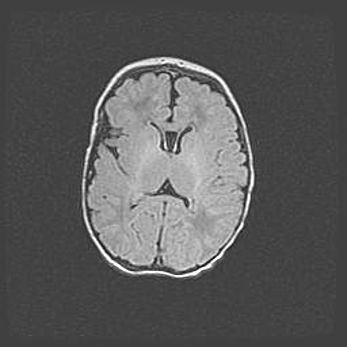

Лейкомаляция с кистозно-глиозной дегенерацией головного мозга.

Возраст: 2 месяца 25 дней

Вес: 6400 г

Окружность головы: 40 см

Срок гестации: 41 неделя

Лейкомаляцию относят к ишемически-гипоксическим повреждениям головного мозга, диагностируемым у новорожденных. При лейкомаляции в головном мозге обнаруживают очаги некроза, возникшие после тяжелой гипоксии и нарушения кровотока. В процессе морфогенеза очаги проходят три стадии: 1) развития некроза, 2) резорбции и 3) формирования глиозного рубца или кисты. Перивентрикулярная лейкомаляция (ПЛ) встречается примерно в 12% случаев среди новорожденных, обычно – у недоношенных детей, причем, частота ее зависит от массы, с которой младенец появился на свет. Наибольшее число малышей страдает лейкомаляцией, если масса при рождении 1500-2500 г.